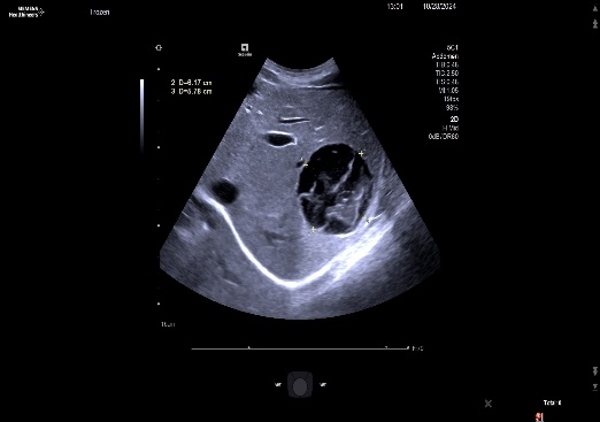

近期阿里地区人民医院收治一名28岁女性患者,体重40Kg,身高140cm,BMI20。以“体检发现肝包虫5年,肝区疼痛1年”之主诉入院。入院后完善B超及上腹部增强CT:肝脏S3段见大小8×7cm囊性病灶,S6、7段见大小约9×8cm 囊性病灶,诊断肝囊型包虫病(CE₃型)。我院援藏队员张立、何鑫、李洪亮及蔡艳组织MDT讨论,制定手术计划,考虑到患者年轻,肝脏体积小,药物作用慢,为防止包虫复发,及术后胆漏合并感染问题,决定采用外囊完整切除的根治性治疗。

11月19日术中联合控制中心静脉压,Pringle法间断阻断肝门,精准定位外囊与肝组织的界限,避免损伤门脉分支及胆管等重要结构,保持囊壁完整性,术中出血约100ml,成功行“肝左叶S3切除,右叶包虫外囊摘除术”。术后患者恢复良好,病理为:外囊完整囊性肿物,内有粉皮样物,符合包虫病。